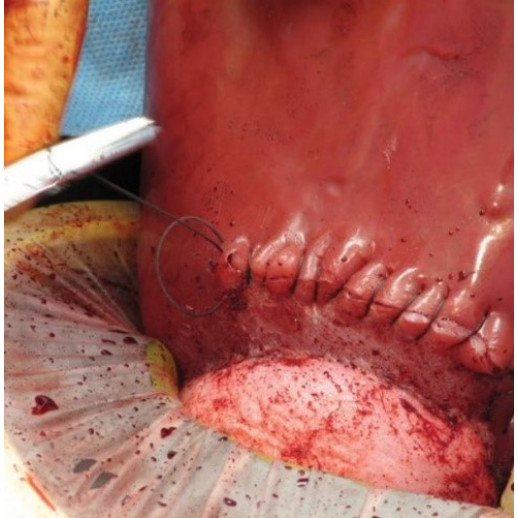

комплект включает в себя не менее 2 маток для выполнения кесарева сечения, выполненных из силикона, имитирующего мышечную структуру матки. комплект должен в себя включать вставки брюшной полости, в количестве не менее 5 шт., выполненных из силикона разной плотности, имитирующего кожный, жировой и мышечный слои. комплект также должен в себя включать комплект для восстановления тканей, позволяющий отрабатывать рассечение мышечных тканей на матках не менее 5 раз на каждой матке. Также комплект восстановления тканей должен позволять проводить восстановление тканей живота (не менее 1 раза). Живот размером 35х37х12 см. – 5 шт. Матка 33 х17 х 13 см. – 2 шт. комплект для восстановления тканей – 1 шт.

Набор искусственных тканей в виде брюшных вставок и имитированных маток позволяет обучающимся отрабатывать навыки отработки рассечения тканей при кесаревом сечении. Матки имитируют структуру мышц с внедрённым сосудом для имитации кровотечения и отработки навыков остановки кровотечения.